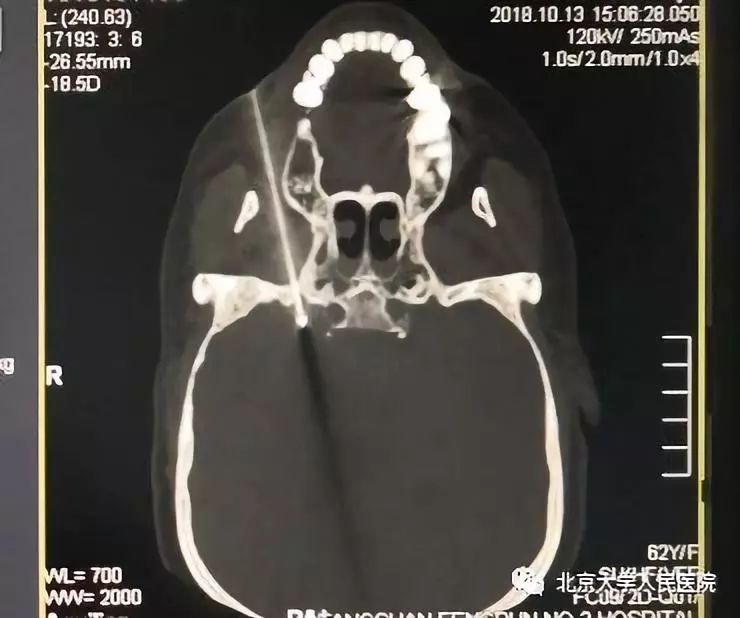

射频热凝治疗三叉神经痛

用特定的射频针,经颅底卵圆孔穿刺至颅内的半月神经节,依靠设定的射频仪能量毁损神经节特定区域,从而长期或永久地阻断疼痛信号向大脑的传递,达到缓解疼痛的目的。射频热凝治疗三叉神经痛的有效率达90%以上。